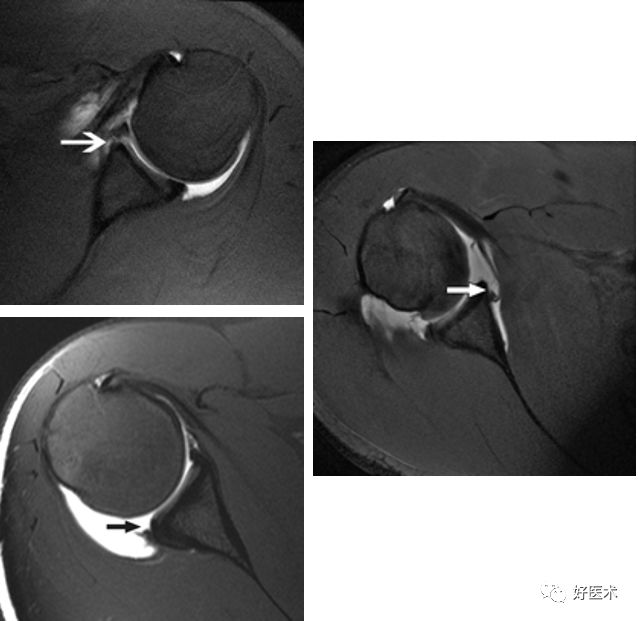

SLAP、Bankart合并Hill-Sach损伤

Hill-Sachs损伤

-

Hill-Sachs损伤:肩关节前脱位时,肱骨头撞向关节盂缘可导致肱骨头的后外侧的嵌插骨折

MR间接关节造影1.5T轴位T1W脂肪抑制

MR间接关节造影1.5T冠状面T1W脂肪抑制

Hill-sachs,Bankart,关节囊损伤